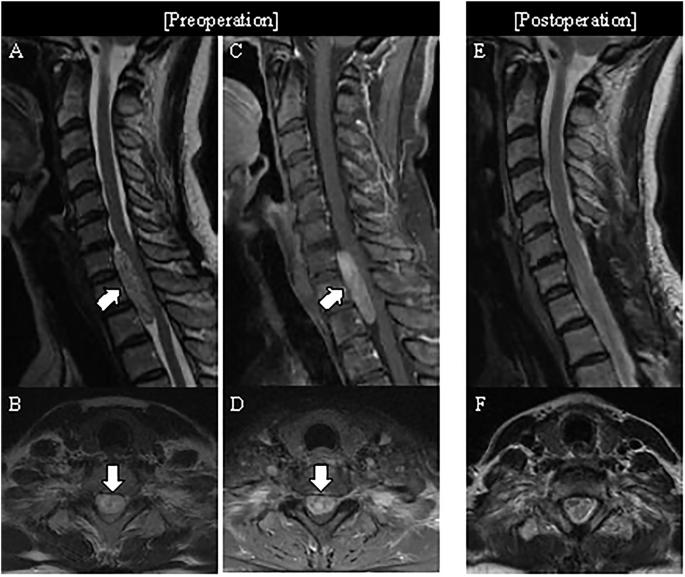

研究设计:回顾性比较研究。目的:比较腹侧硬膜内髓外(IDEM)神经鞘瘤与背侧/外侧IDEM神经鞘瘤的手术和临床结果。背景:日本唯一的机构。方法:本研究纳入了94例2012年至2022年间经后路手术切除的颈椎或胸椎IDEM神经鞘瘤患者。根据肿瘤定位将患者分为腹侧组(n = 12)和背侧组(n = 82)。评估人口统计学和外科数据,包括手术时间和术中运动诱发电位(MEP)变化,以及临床结果,如日本骨科协会(JOA)评分和步态功能(改良McCormick量表,MMCS)。结果:与背侧组相比,腹侧组手术时间明显更长(p = 0.039),术中MEP波形更有可能短暂下降(p = 0.008)。然而,在手术年龄、性别、水平、肿瘤大小、估计失血量、JOA评分改善、JOA恢复率或最终随访时的步态功能方面,两组之间没有显著差异。所有病例均获得全切除(GTR)。结论:尽管手术时间更长,术中MEP波形更有可能暂时下降,但与背侧/外侧IDEM神经鞘瘤相比,腹侧IDEM神经鞘瘤的手术或临床结果并不明显差。这些发现表明,即使手术过程需要更长的时间,经后路大体切除腹侧神经鞘瘤也会产生良好的治疗效果。